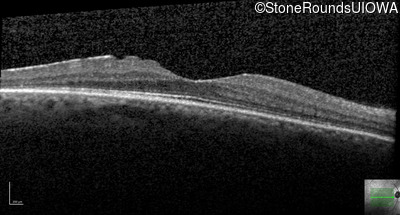

Optical Coherence Tomography - Left - 20/25

Exemplar / OCT Stack

OCT Stack